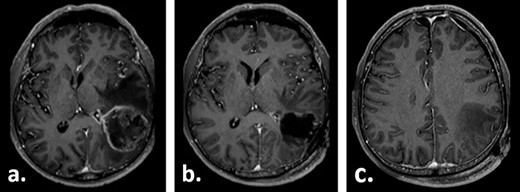

Ten weeks postoperatively, the patient complained of vertigo and a self-limiting episode of right-sided visual field restriction and neglect. Subsequently, oral cortisone therapy was started again, which lead to the relief of these symptoms. The MRI showed a new contrast enhancement around the resection cavity, possibly treatment-related after radiochemotherapy, as well as a 14-mm-thick, left-sided subdural fluid collection causing a midline shift of 6 mm, which was interpreted as a subdural hygroma or hematoma (Fig. 2). The latter was slightly progressive on a CT scan 1 week later, and surgical evacuation through a burr hole was indicated. Intraoperatively, it presented as a slightly xanthochrome, slightly pressurized subdural hygroma. No pathological alterations of the dura were revealed during this procedure. Postoperatively, the subdural hygroma was incompletely regressive and began to grow again as was seen on the CT images 3 weeks after the surgery. This finding was considered to be related to post-radiation changes. The patient stayed asymptomatic and received two cycles of adjuvant chemotherapy with temozolomide 150 mg/m2 body surface area and 200 mg/m2 body surface, respectively.

Gadolinium-enhanced T1-weighted axial MRI of the patient 10 weeks after tumour resection demonstrating the resection cavity (a) and new subdural fluid collection (b).